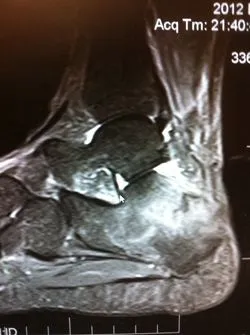

MRI imaging is excellent for diagnosing stress fractures. A T1 weighted image will show normal bone in a white color and edema and/or fracture lines in gray to black color (below left). T2 weighted imaged are the opposite and will show bone black and any fluid like swelling within the bone or throught a fracture as white (below right).